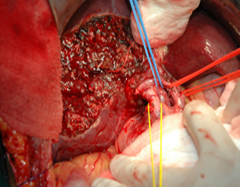

Majority of Gallbladder cancers are associated with gallstones (80%). Symtoms may be similar to gallstone disease. It is imperitive that the surgeon sees every specimen of the Gall bladder removed for stones to identify early cancer in the operating room itself so as to initiate further treatment without delay. Jaundice in patients usually indicates an advanced disease and very often a guarded prognosis. Outcome is best for early GBC, and those with limited invasion in the surrounding organs like the liver & duodenum. Surgery varies from a radial cholecystectomy. (GB + lymphadenectomy + liver tissue from GB base) to segmental hepatectomy (4a +5) to extended hepatectomy. (Right trisegmentectomy) for advanced disease.